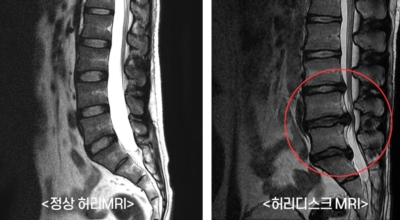

여러 개의 작은 척추뼈가 모여서 척추라는 신체의 기둥을 이루게 돼요. 척추뼈 사이에는 척추뼈끼리 부딪치는 것을 방지하는 쿠션 같은 역할을 하는 '디스크(disc)'라는 말랑말랑한 젤리 같은 구조물이 있는데 우리말로는 '추간판'이라고 합니다.

디스크(추간판)의 한가운데에는 젤리같이 찐득찐득한 '수핵'이라 하는 물질이 들어 있어요. 그 주변에 수핵을 둘러싸는 '섬유륜'이라 하는 두꺼운 막이 있는데 디스크는 전체적으로 자동차의 타이어와 같은 형태라고 합니다.

디스크는 일어선 상태에서는 중력을 받아 납작해져서 바깥쪽으로 약간 볼록한 형태가 된다고 합니다. 디스크는 그 특수한 구조 때문에 웬만한 힘이 가해져도 효율적으로 쿠션 역할을 할 수 있겠습니다. 그러나 급작스럽게 무거운 물건을 들어 올리거나, 부자연스러운 자세를 오랜 시간 취하면 디스크에 무리한 힘이 가해지면서 디스크가 밖으로 돌출이 되게 돼요. 심한 경우 디스크를 감싼 막이 터지면서 그 안에 있는 수핵이 튀어나오게 돼요.

디스크는 대개 후방이나 후외방으로 돌출되는데 이때 바로 곁에 있는 신경을 누르게 된다고 합니다. 돌출된 디스크는 척추의 어느 부위에나 일어날 수 있어요. 목에 생기면 '목 디스크', 등에 생기면 '등 디스크', 허리에 생기면 '허리 디스크'라고 부른다고 합니다.

이와 같이 디스크가 돌출되어 신경을 눌러 요통 또는 다리가 아프고 저린 증상을 유발하는 병을 '추간판 탈출증' 및 '디스크 탈출증'이라고도 불러요. 발생 빈도별로 보면 허리 디스크가 가장 흔합니다. 그다음이 목 디스크이지요. 등 디스크는 드문 병이라고 합니다.